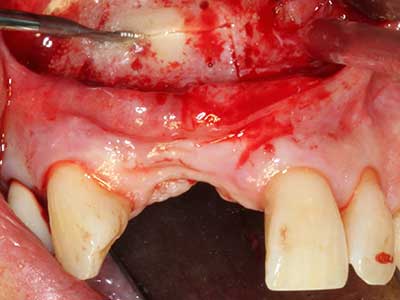

La piezochirurgia presenta altri vantaggi per quanto riguarda la raccolta di blocchi ossei. Oltre all'elevata precisione dell'osteotomia appena descritta, l'utilizzo di puntine per sega molto sottili permette di minimizzare in maniera significativa la perdita di materiale. È molto probabile che si verifichi una maggiore perdita di materiale durante la raccolta utilizzando puntine di strumenti più spessi, in particolare delle frese Lindemann (Lakshmiganthan, Gokulanathan et al. 2012). La separazione basale, necessaria in particolare per i trapianti di blocchi nella zona retromolare, viene semplificata grazie a seghe specificatamente progettate di forma rettangolare; di conseguenza la piezochirurgia è considerata una procedura precisa, semplice e sicura per la raccolta di blocchi di osso nella zona retromolare (Happe 2007) (figg. 1-12).